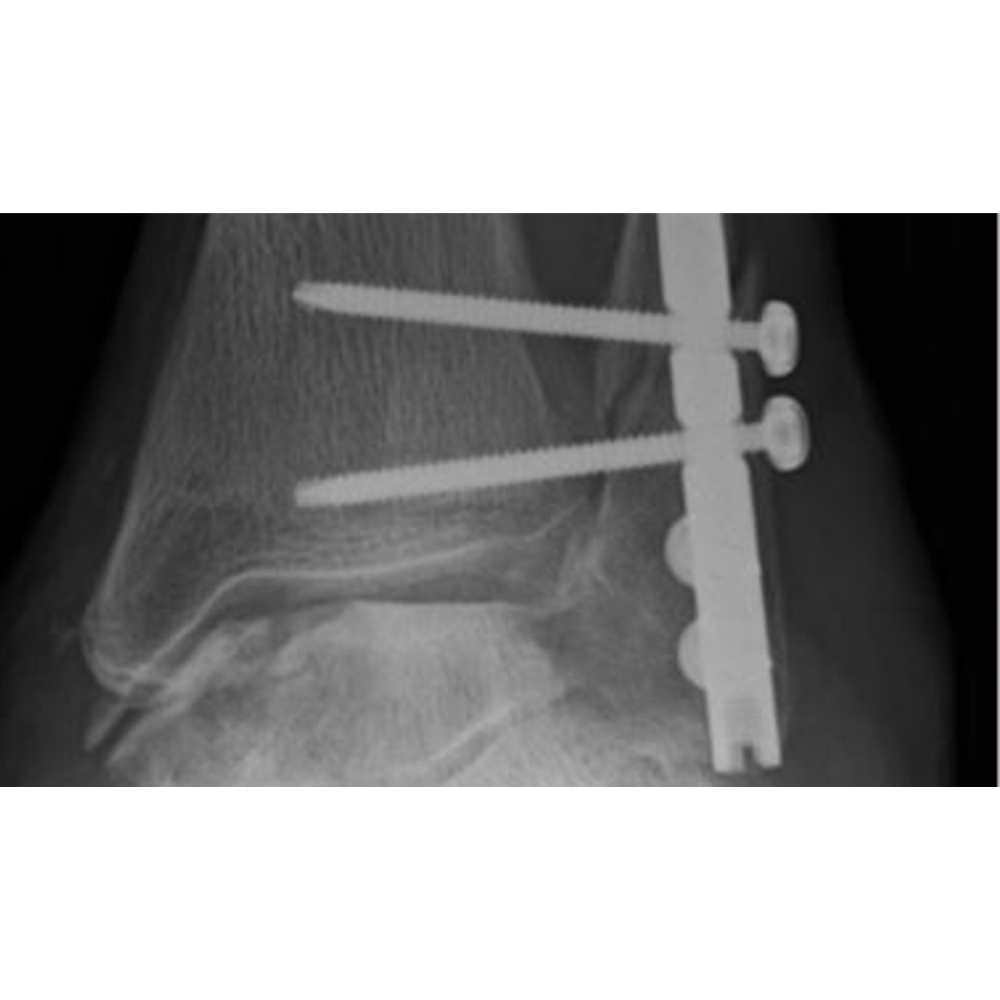

Voorbeelden van gebruik

Postoperatieve Postoperatieve